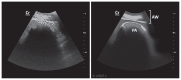

The purpose of this study was to develop a method for identification of the pylorus, in lactating Holstein cows, based on ultrasound examination and the use of external anatomical landmarks such as the mammary vein (anulus venae subcutaneae abdominis). An ultrasound method based on successive identification of 4 internal anatomical landmarks was developed. The procedure was performed 157 times, on clinically healthy lactating Holstein cows, with a portable ultrasound machine equipped with a 3.5 MHz curvilinear probe. The pylorus was identified with a success rate of 98.7% (155 times out of 157 procedures). The average position of the pylorus was noted near the entrance of the right mammary vein, with a craniocaudal and dorsoventral dispersion. This ultrasound method of identifying the pylorus is simple, effective, and rapid.